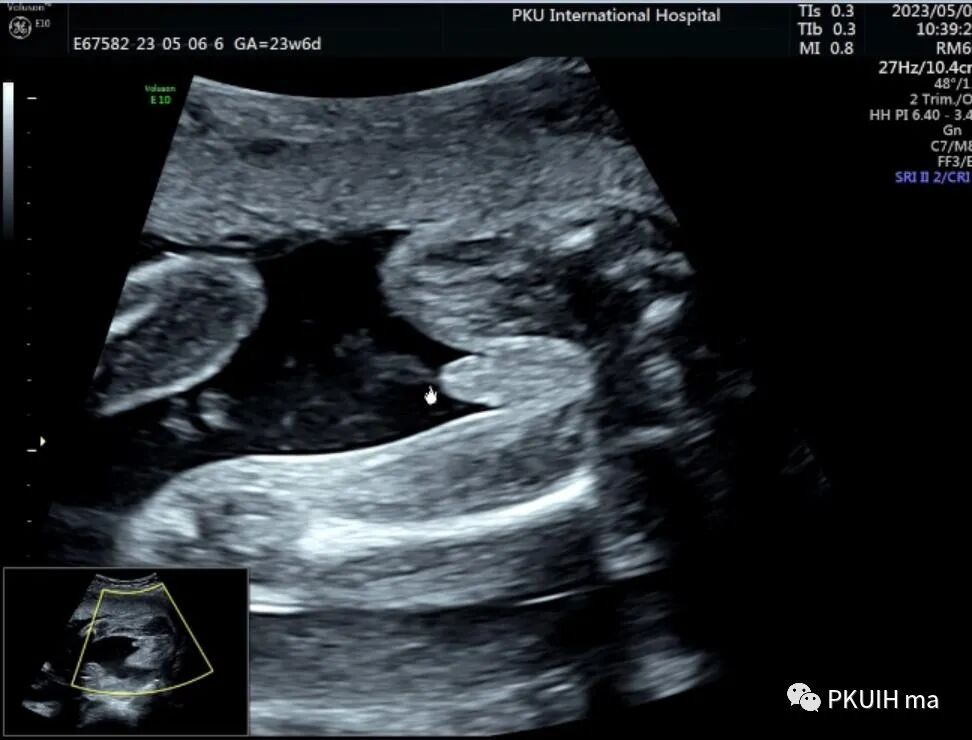

今天跟大家分享一个马蹄肾胎儿,23周常规系统排畸,矢状切发现胎儿肾脏偏长,下极边界相对不清晰,横断面发现肾盂有点轻度分离,但肾盂分离的方向有点不对劲,随仔细观察胎儿双肾。

矢状面肾下极轮廓不清,肾的位置相对偏低